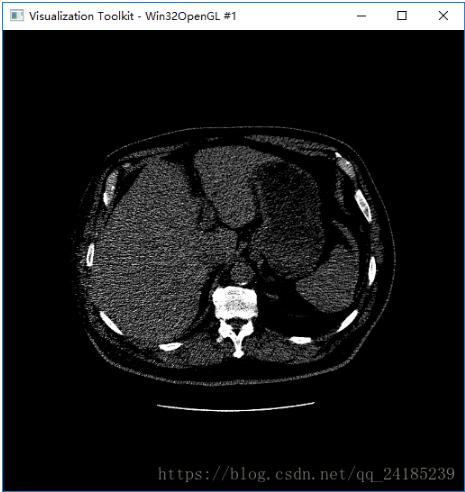

运行程序得到显示图: